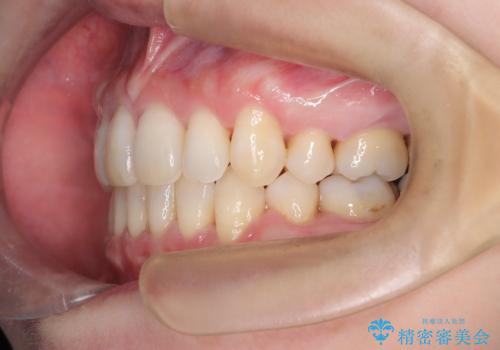

前歯が前に出ていることや歯並びの凸凹が気になるという主訴でした。十分なスペースを確保するため上下左右の第一小臼歯(4番)を抜歯し、そこに前歯を移動させて整列を行いました。矯正装置には目立ちにくい透明なブラケットを選択し、見た目のストレスを軽減。矯正期間中は定期的な通院でワイヤーを微調整し、無理なく確実に歯を動かしました。治療後は前歯が自然な位置に下がり、口元の突出感が解消されるとともに、美しく整った口元に仕上がり、患者様にも大変喜んでいただけました。